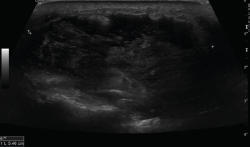

2.2. Roturas

Se observan áreas hipoecoicas de solución de continuidad de las fibras tendinosas(7), con retracción de los márgenes con la contracción muscular cuando la rotura tendinosa es completa (Figuras 9 y 10).

Figura 9. Corte sagital de una ecografía de rodilla: foco hipoecoico por rotura parcial del tendón cuadricipital.

Figura 10. Corte sagital de una ecografía de rodilla: ausencia del tendón rotuliano por rotura completa, con hematoma señalado en el trayecto del tendón.